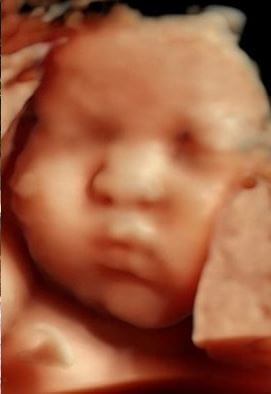

진태현은 당시 인스타그램을 통해 "임신 마지막 달, 폭우와 비바람의 날씨가 끝나고 화창한 정기 검진날, 우리 베이비 태은이가 아무 이유 없이 심장을 멈췄다"며 아이를 잃은 슬픔을 털어냈습니다. 아이는 정확히 20일 후에 세상에 나올 예정이었던 아이였습니다.

"9개월 동안 아빠와 엄마에게 희망과 사랑을 줬고, 모든 걸 다 줬지만 얼굴은 보여주지 않고 떠났다"고 그는 말했습니다.